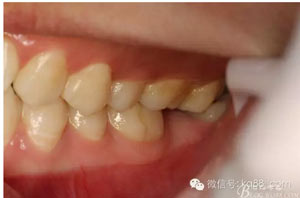

圖3。閉口位,27與38有咬合接觸。因此,保留38、拔除37.防止囊性變進(jìn)一步擴(kuò)大。

3.jpg